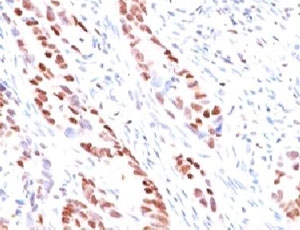

IHC testing of human prostate carcinoma and p57 antibody (clone KIP57-1). Staining of formalin-fixed tissues requires boiling tissue sections in pH 9 10mM Tris with 1mM EDTA for 10-20 min followed by cooling at RT for 20 min.

IHC testing of human colon carcinoma and p57 antibody (clone KIP57-1). Staining of formalin-fixed tissues requires boiling tissue sections in pH 9 10mM Tris with 1mM EDTA for 10-20 min followed by cooling at RT for 20 min.